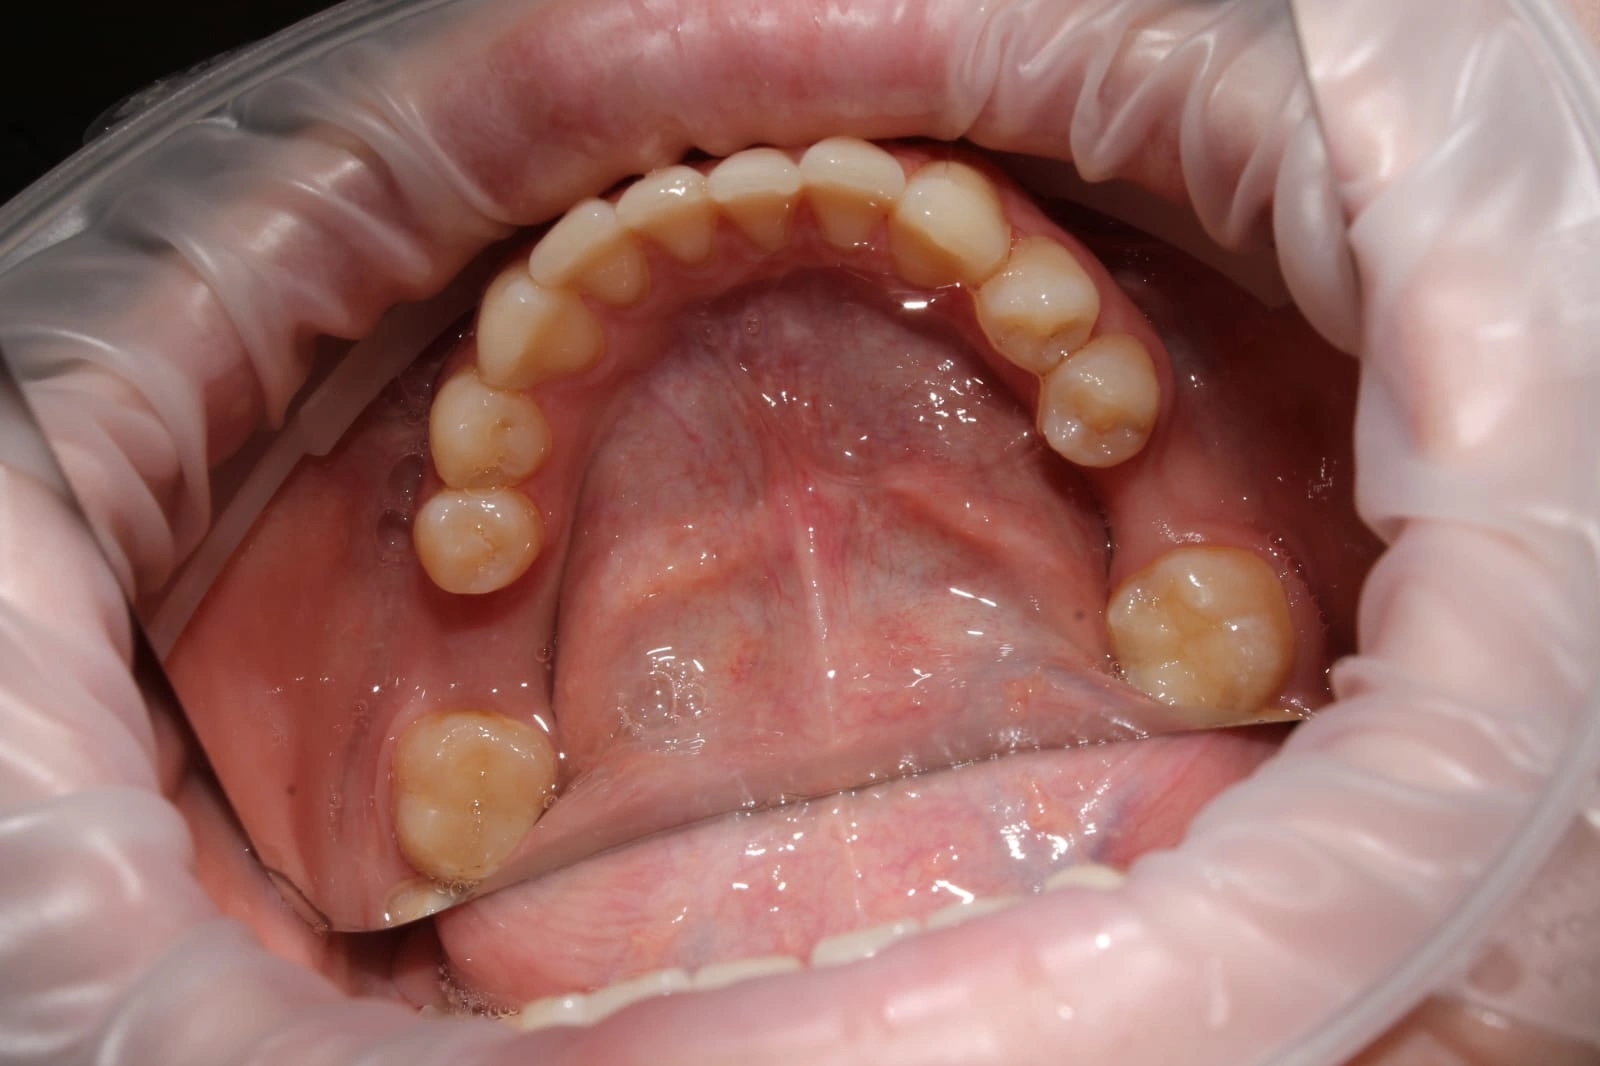

Laser Dentistry is a modern treatment approach that uses focused light energy to perform dental procedures with high precision. This allows dentists to treat tissues gently, with minimal cutting, reduced bleeding, and faster healing all while keeping patient comfort at the centre.

Some of the most commonly performed procedures in Dentistry include

Gently reshapes excess gum tissue for a balanced, natural-looking smile.

Removes excess gum tissue (and minor bone if required) to expose more of the tooth.